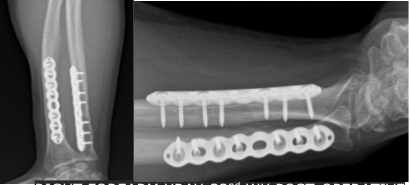

Right Forearm X-ray-1st week post-operative